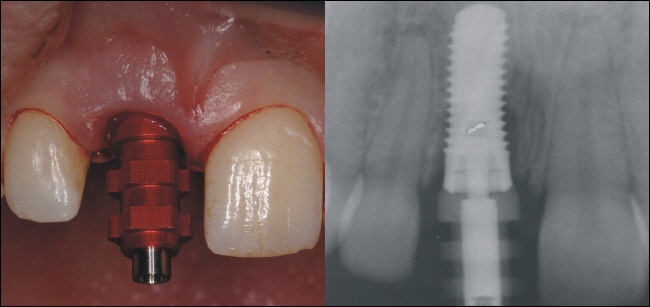

Sofortimplantation

Da in diesem Fall die Knochenstruktur komplett erhalten war, konnte in das Zahnfach direkt ein passendes Implantat eingebracht werden. Das linke Bild zeigt die optimale Positionierung, der Hilfspfosten (Einbringpfosten) des Implantates ist noch auf dem Implantat moniert.